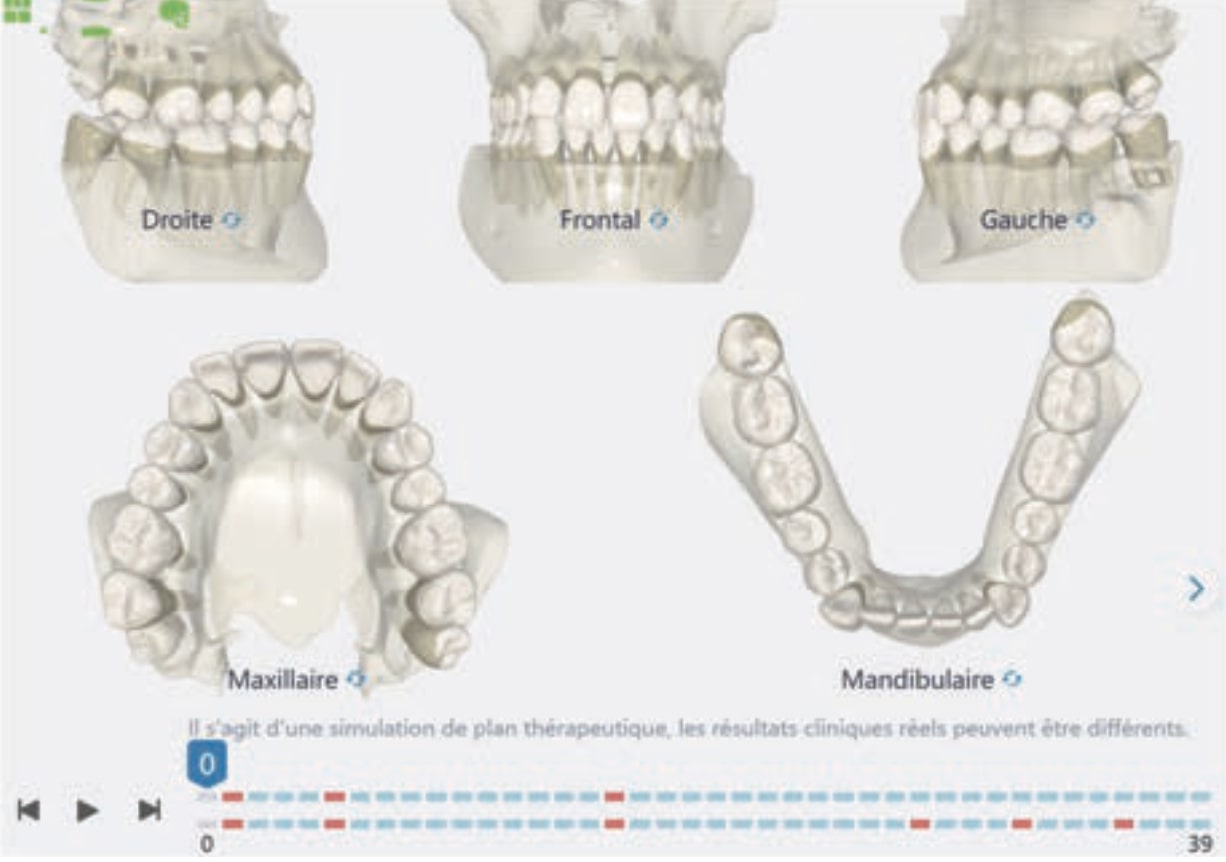

Number of aligners: 39

Treatment setup